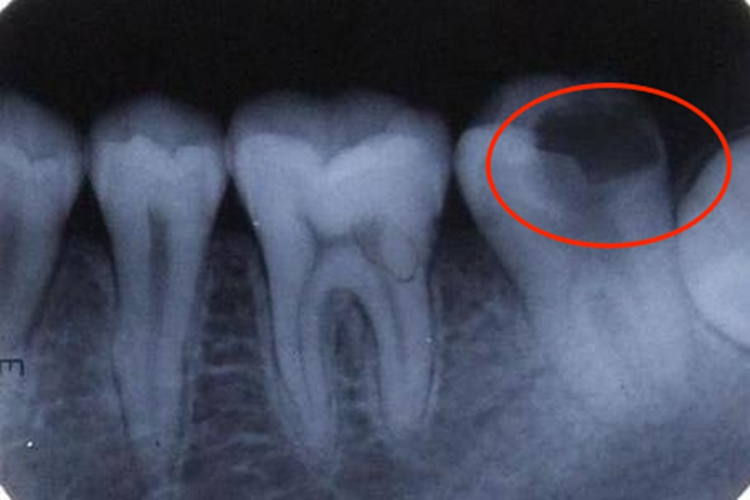

儿童牙齿牙片出现异常表现主要见于龋齿及乳牙滞留,儿童龋齿可见牙片上单个或多个牙齿釉面出现缺损,牙体硬组织显示出透射度增大的阴影,局部可有龋洞。儿童发生乳牙滞留时,可见双排牙现象,常见于下颌乳中切牙滞留,恒中切牙于乳中切牙舌侧萌出。